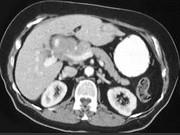

问题 女,40岁,右上腹痛,进行性黄疸,腹部未触及包块,AFP阴性,影像检查如图,最可能的诊断是()

选项 A.肝细胞肝癌 B.胆总管癌 C.胰头癌 D.胰岛细胞瘤 E.慢性胰腺炎

答案 B